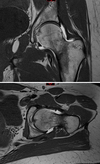

Figure 1 is the MRI scan of a 15-year-old boy who has had knee pain with running for 5 months. What is the most appropriate treatment?

Arthroscopic or open reduction and internal fixation ## Footnote OCD is an acquired lesion of the subchondral bone. Patients with OCD initially report nonspecific pain and variable amounts of swelling. **Initial radiographs help identify the lesion and establish the status of the physes**. An MRI scan is useful for assessing the potential for the lesion to heal with nonsurgical treatment. **Nonsurgical treatment is appropriate for small, stable lesions in patients with open physes and focuses on activity restriction for 3 to 9 months**. Surgical treatment is necessary for unstable or detached lesions. Stable lesions with intact articular cartilage can be treated with subchondral drilling to stimulate vascular ingrowth, with radiographic healing at an average of 4.4 months. Fixation is indicated for unstable or hinged lesions, and stabilization of the fragment can be achieved using a variety of implants through an arthroscopic or open approach. The fragment should be salvaged and the normal articular surface restored whenever possible.